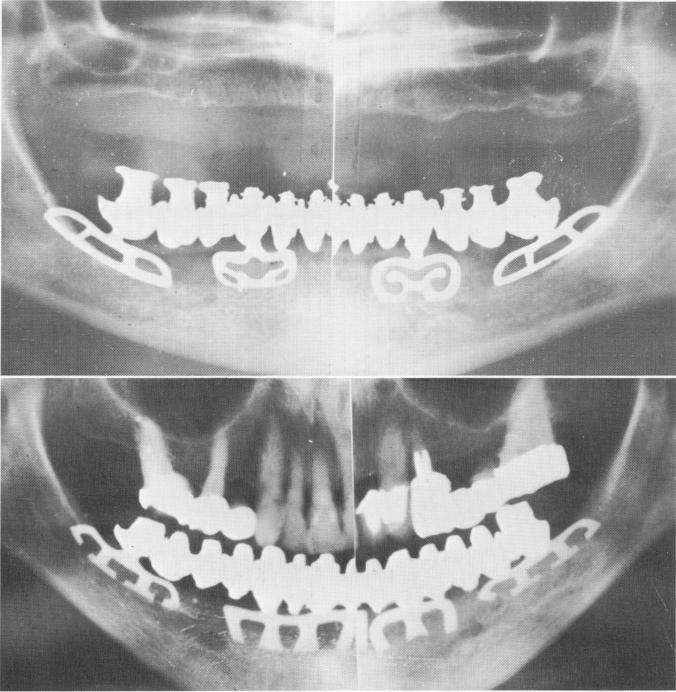

Today titanium blades* are manufactured that allow the operator to easily bend the necks or the blade itself to fit into a curved groove. It also be-comes quite simple to grind away portions of the posts for parallelism. Fig. 11-146, B, shows the parallelism that is readily attained with titanium blades in another edentulous mandible.

Fig. 11-146. A, The final Panorex. (From Linkow, L. I., and Weiss, J. L.: The endosseous blade: a progress report, Prom. Dent., No. 5, 1969.) B, Another case using blade implants as the only supports for a fixed full arch denture in the completely edentulous mandible opposing a natural upper dentition.